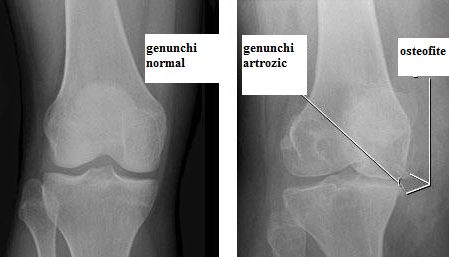

Gonartroza – Radiografie cu genunchi artrozic

Se trece apoi la examenul imagistic. De obicei examenul radiologic este suficient pentru a pune diagnosticul de gonartroză. Un examen radiologic corect se efectuează cu pacientul în ortostatism (în picioare), acesta lăsând greutatea pe membrul de examinat. Astfel se proiectează imaginea genunchiului aşa cum este el solicitat. Se obţin, prin această metodă, mai multe informaţii decât dacă pacientul ar fi examinat în clinostatism (culcat), deoarece se percepe indirect şi starea ligamentelor din jurul articulaţiei. O altă procedură radiologică este aceea de a efectua radiografia întregului membru inferior. Aceasta este necesară pentru a identifica eventualele modificări de ax ale segmentelor osoase. Aceste examene amănunţite sunt necesare mai ales atunci când se face pregătirea preoperatori pentru artroplastie(LINK la pagina de proteza genunchi).